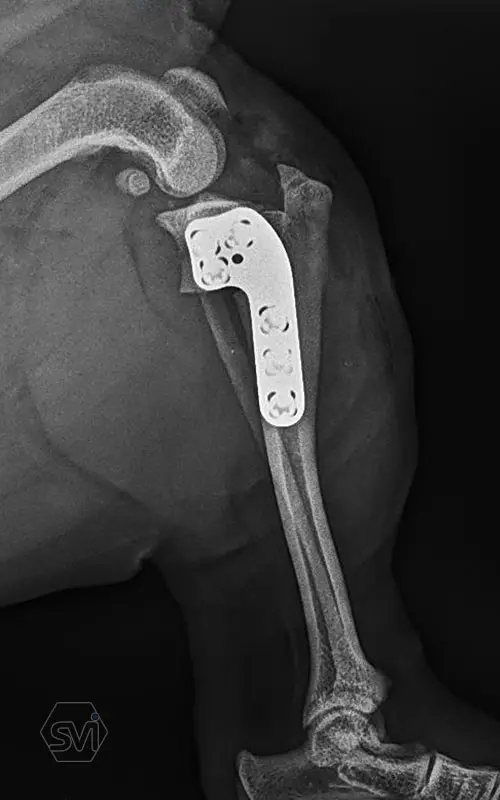

Introducing the precontured polyaxial locking TPLO family, now available in all sizes:

- Mini: 2.0mm (thinner and thicker version)

- Midi: 2.4mm

- Small: 2.7mm

- Standard: 3.5mm (both in short and extended versions)

- Giant: designed for 4.0mm screws.

It has a number of advantageous features that make it stand out from standard TPLO solutions:

- well designed that follows the anatomical position and ideal hole placement

- precontoured, its use shortens the surgical time, no greater physical force is required for bending

- locking system for greater stability

- polyaxial screw insertion, the direction of screw insertion can be freely selected in a 30-degree circle while maintaining angular stability! (this is very useful to avoid driving the screw into the joint, and the temporary fixing can also be avoided with a K-wire)